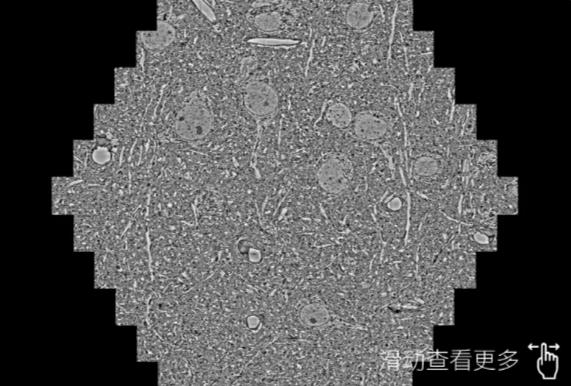

鼠脑切片。左图使用太原蔡司太原扫描电镜MultiSEM706对165μmx143pm面积区域成像,耗时仅需1.5秒。右图为鼠脑切片中30μm区域放大效果。样品由芝加哥大学B.Kasthuri提供。

使用蔡司高速太原扫描电镜MultiSEM对1mm²人脑皮层组织进行高分辨成像,并对其中的各种细胞结构进行三维重构分析。左图展示了2x3mm²组织平面中锥体神经元的三维重构效果。右图显示了局部体积神经元三维重构。图像由哈佛大学chtman实验室提供,渲染图由D. Berger 制作。